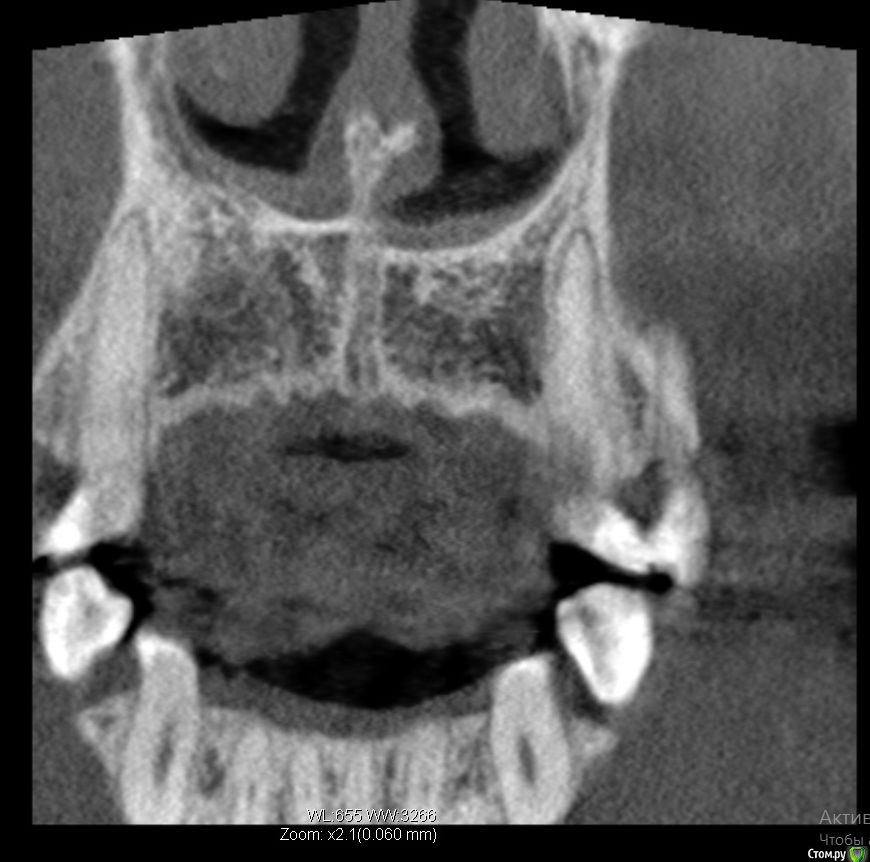

Bier Опубликовано 21 апреля, 2017 Поделиться Опубликовано 21 апреля, 2017 3д реконструкция нам не подходит. Хотя по ней все довольно печально выглядит.покажите скриншоты срезов. Ссылка на комментарий

колесников Опубликовано 21 апреля, 2017 Поделиться Опубликовано 21 апреля, 2017 Резецировать там нечего,во время эндодонтического лечения произошла перфорация стенки корня зуба,вокруг этого участка очаг деструкции костной ткани. Это не лечится.По выставленной вами картинке объём деструкции не понятен. Решить возможность одномоментной имплантации и тем более немедленной нагрузки может только ваш лечащий доктор ,по результатам кт и в соответствии со своим опытом. Ссылка на комментарий

Lanasvlisa Опубликовано 22 апреля, 2017 Автор Поделиться Опубликовано 22 апреля, 2017 Здравствуйте, уважаемые врачи, и спасибо большое вам за оперативные ответы! Я не знаю, как найти срезы, полагаю, проекции - это то же самое, что и срезы? Я сделала их скриншоты+ еще три фото. А если я все-таки отправлю ссылку на весь архив, вы бы могли оценить объем разрушения костной ткани, чтобы предположить, насколько реально провести имплантацию в день удаления? У меня еще такие вопросы: если имплантацию удается провести сразу, то 1) через какой срок можно в моем случае заняться установкой коронки; 2) какая она должна быть; 3) если придется пользоваться "бабочкой" (я так понимаю, это единственный вариант, все временные коронки, в том числе клеевые, - это нагрузка, а каппа сюда тоже не подойдет?), то как потом происходит восстановление формы десны? Можно ли как-то сохранить десневые сосочки в случае отсроченной имплантации? Спасибо большое! Ссылка на комментарий